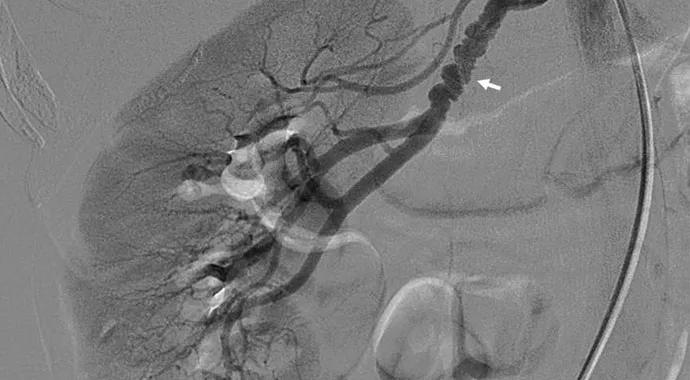

medial_fibroplasia_690x380

• FMD is a disease of the cerebrovascular vessels, as much as the renal vessels. Two-thirds of renal FMD patients have carotid or vertebral disease, as well.

• Approximately one in three FMD patients experiences an aneurysm or dissection. “It’s important to check patients for aneurysms from the top of the head to the pelvis,” says Dr. Gornik.